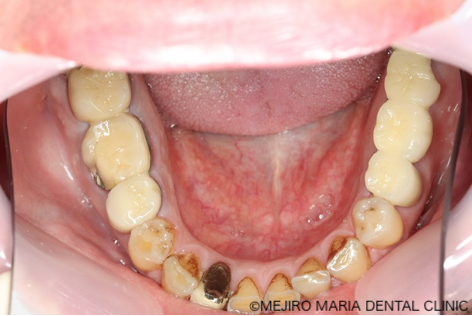

まずは、歯周組織検査を含めた口腔内診査、レントゲン写真の撮影により、保存できる歯牙と、抜歯をせざるを得ない歯牙などを選定しました。

当院では精密根管治療により、ほとんどの歯牙の保存が可能なことから、最初の段階では、明らかな歯根破折が確認される場合のみ抜歯の診断をしています。精密根管治療を行っても、歯牙保存による費用対効果が低いと考えられる場合は、その都度患者様と相談の上、歯牙を保存するか抜歯するか選択していきます。

今回の症例では、歯根破折していた5本の歯牙(下の写真・赤矢印)に対して、抜歯を提案した。また、診断用WaxUp(ワックスアップ)を行ったところ左下のブリッジ(青丸)と右下(青矢印)の噛み合わせ平面が乱れており、咬合に負担をかけていることが予想されました。そのため、最終的にそれらの不調和を改善し、適切な噛み合わせにすることをゴールとして治療を開始しました。

そのため、抜歯の際はまず口腔外科医が不良肉芽を確実に除去します。その後、骨がインプラント埋入に耐えられるよう、インプラント専門医がGBR(骨造成)やソケットリフトを施して不足している骨の再生治療を行ってから、インプラントを安全に埋入しました。そのほか、既に根管治療済みの歯で保存できると判断したものは、精密根管治療専門医が保存の処置をしました。